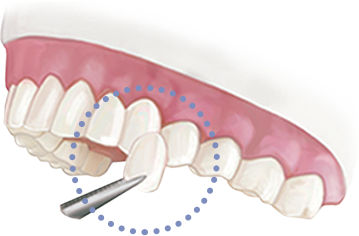

연세그리다치과에서는 3D CT로 정밀 진단하여,

사랑니의 전후방 좌우 위치를 파악하고

해부학적 구조물과 연관성을 분석한 후

안정적인 사랑니 발치가 되도록 최선을 다합니다.

*단, 염증 상태에 따라 의료진의 판단하에 불가할 수도 있습니다.